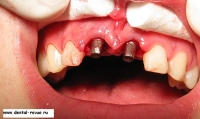

12. Вид установленных имплантатов Bicon с заглушками.